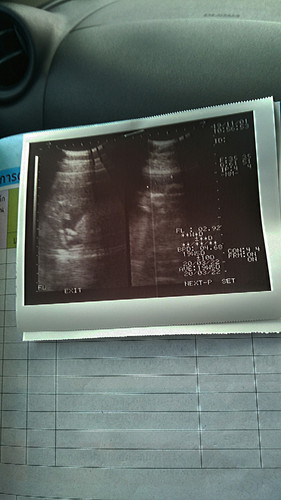

ลุงหมอบอกหนูเป็นผู้ชายแต่อีแม่ดูไม่เป้น555

บ้านในกำหนดมีนาได้เพศไหนกันค่ะ โชว์กันหน่อยจ้า.??